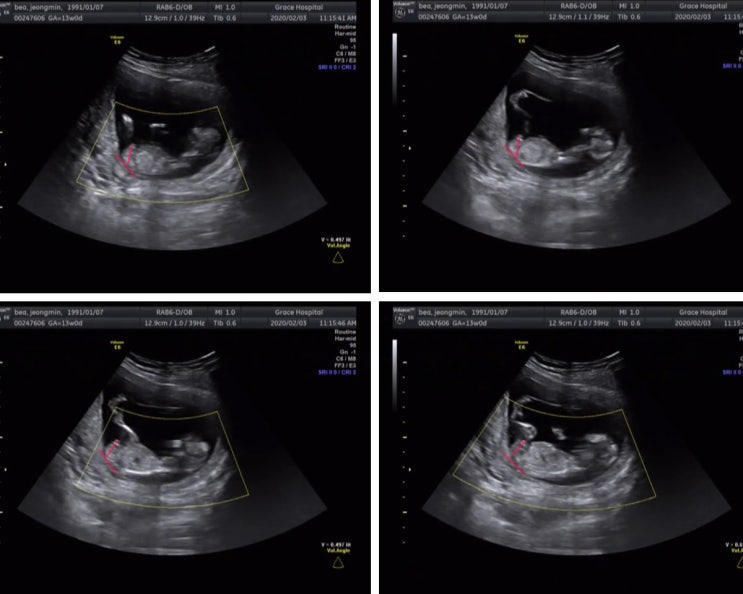

12주 각도법과 태몽으로 예측했던 성별 기록

지금 우리 꾹밥이는 27주를 지나고 있고, 입덧과 임신 적응으로 기록해 두지 못했던 12주 초음파로 감별해...